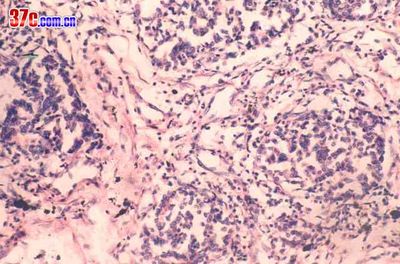

肺炎性假瘤是成纤维细胞.淋巴细胞.浆细胞.异物巨细胞.组织细胞及泡沫细胞等组成的肉芽肿。

肺炎性假瘤(inflammatory pseudotumor)①:胆固醇肺炎,示肺泡间隔内由淋巴细胞增生聚集而成的小团块,像花蕾样突入肺泡道内,略似淋巴滤泡,但无生发中心。he×200。

肺炎性假瘤(inflammatory pseudotumor)②:示肺泡腔内的泡沫细胞。he×400。

肺炎性假瘤(inflammatory pseudotumor)③:示巨噬细胞、泡沫细胞、淋巴细胞及浆细胞。有些巨噬细胞胞浆含有含铁血黄素颗粒。he×400。

肺炎性假瘤(inflammatory pseudotumor)④:肺浆细胞肉芽肿,肉芽组织内主要为成熟性浆细胞,此外,还可见淋巴细胞及泡沫细胞等。he×200。

肺炎性假瘤(inflammatory pseudotumor)⑤:正常组织结构消失,纤维结缔组织广泛增生,肺泡上皮细胞增生形成假腺腔样结构。

肺炎性假瘤(inflammatory pseudotumor)⑥:肺泡及支气管结构消失,而呈炎性肉芽组织构像。he×100。